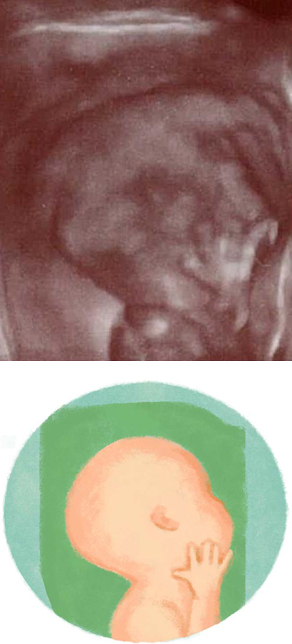

妊娠17週ころの超音波写真

筋肉と神経が発達します

肩などがしっかりしてきて手足の動きが複雑になってきたのは、筋肉と神経が発達してきた証し。赤ちゃんが伸ばした手足が子宮壁に触れることで、やがて胎動を感じるようになります。